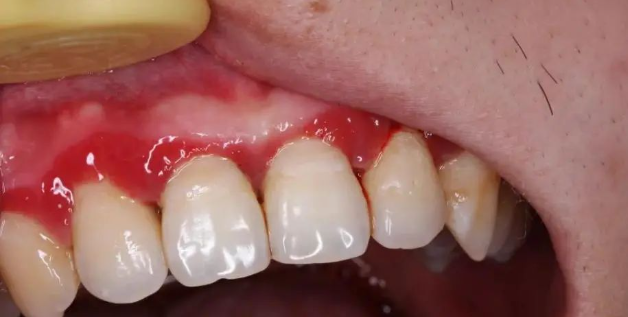

一开始出现的症状大概率是:牙龈有点发红、刷牙的时候有点出血,或者啃一口苹果后发现留下了一圈血印子。

刚开始,仅仅是出现牙龈红肿及出血,并不一定导致疼痛,图源:作者提供